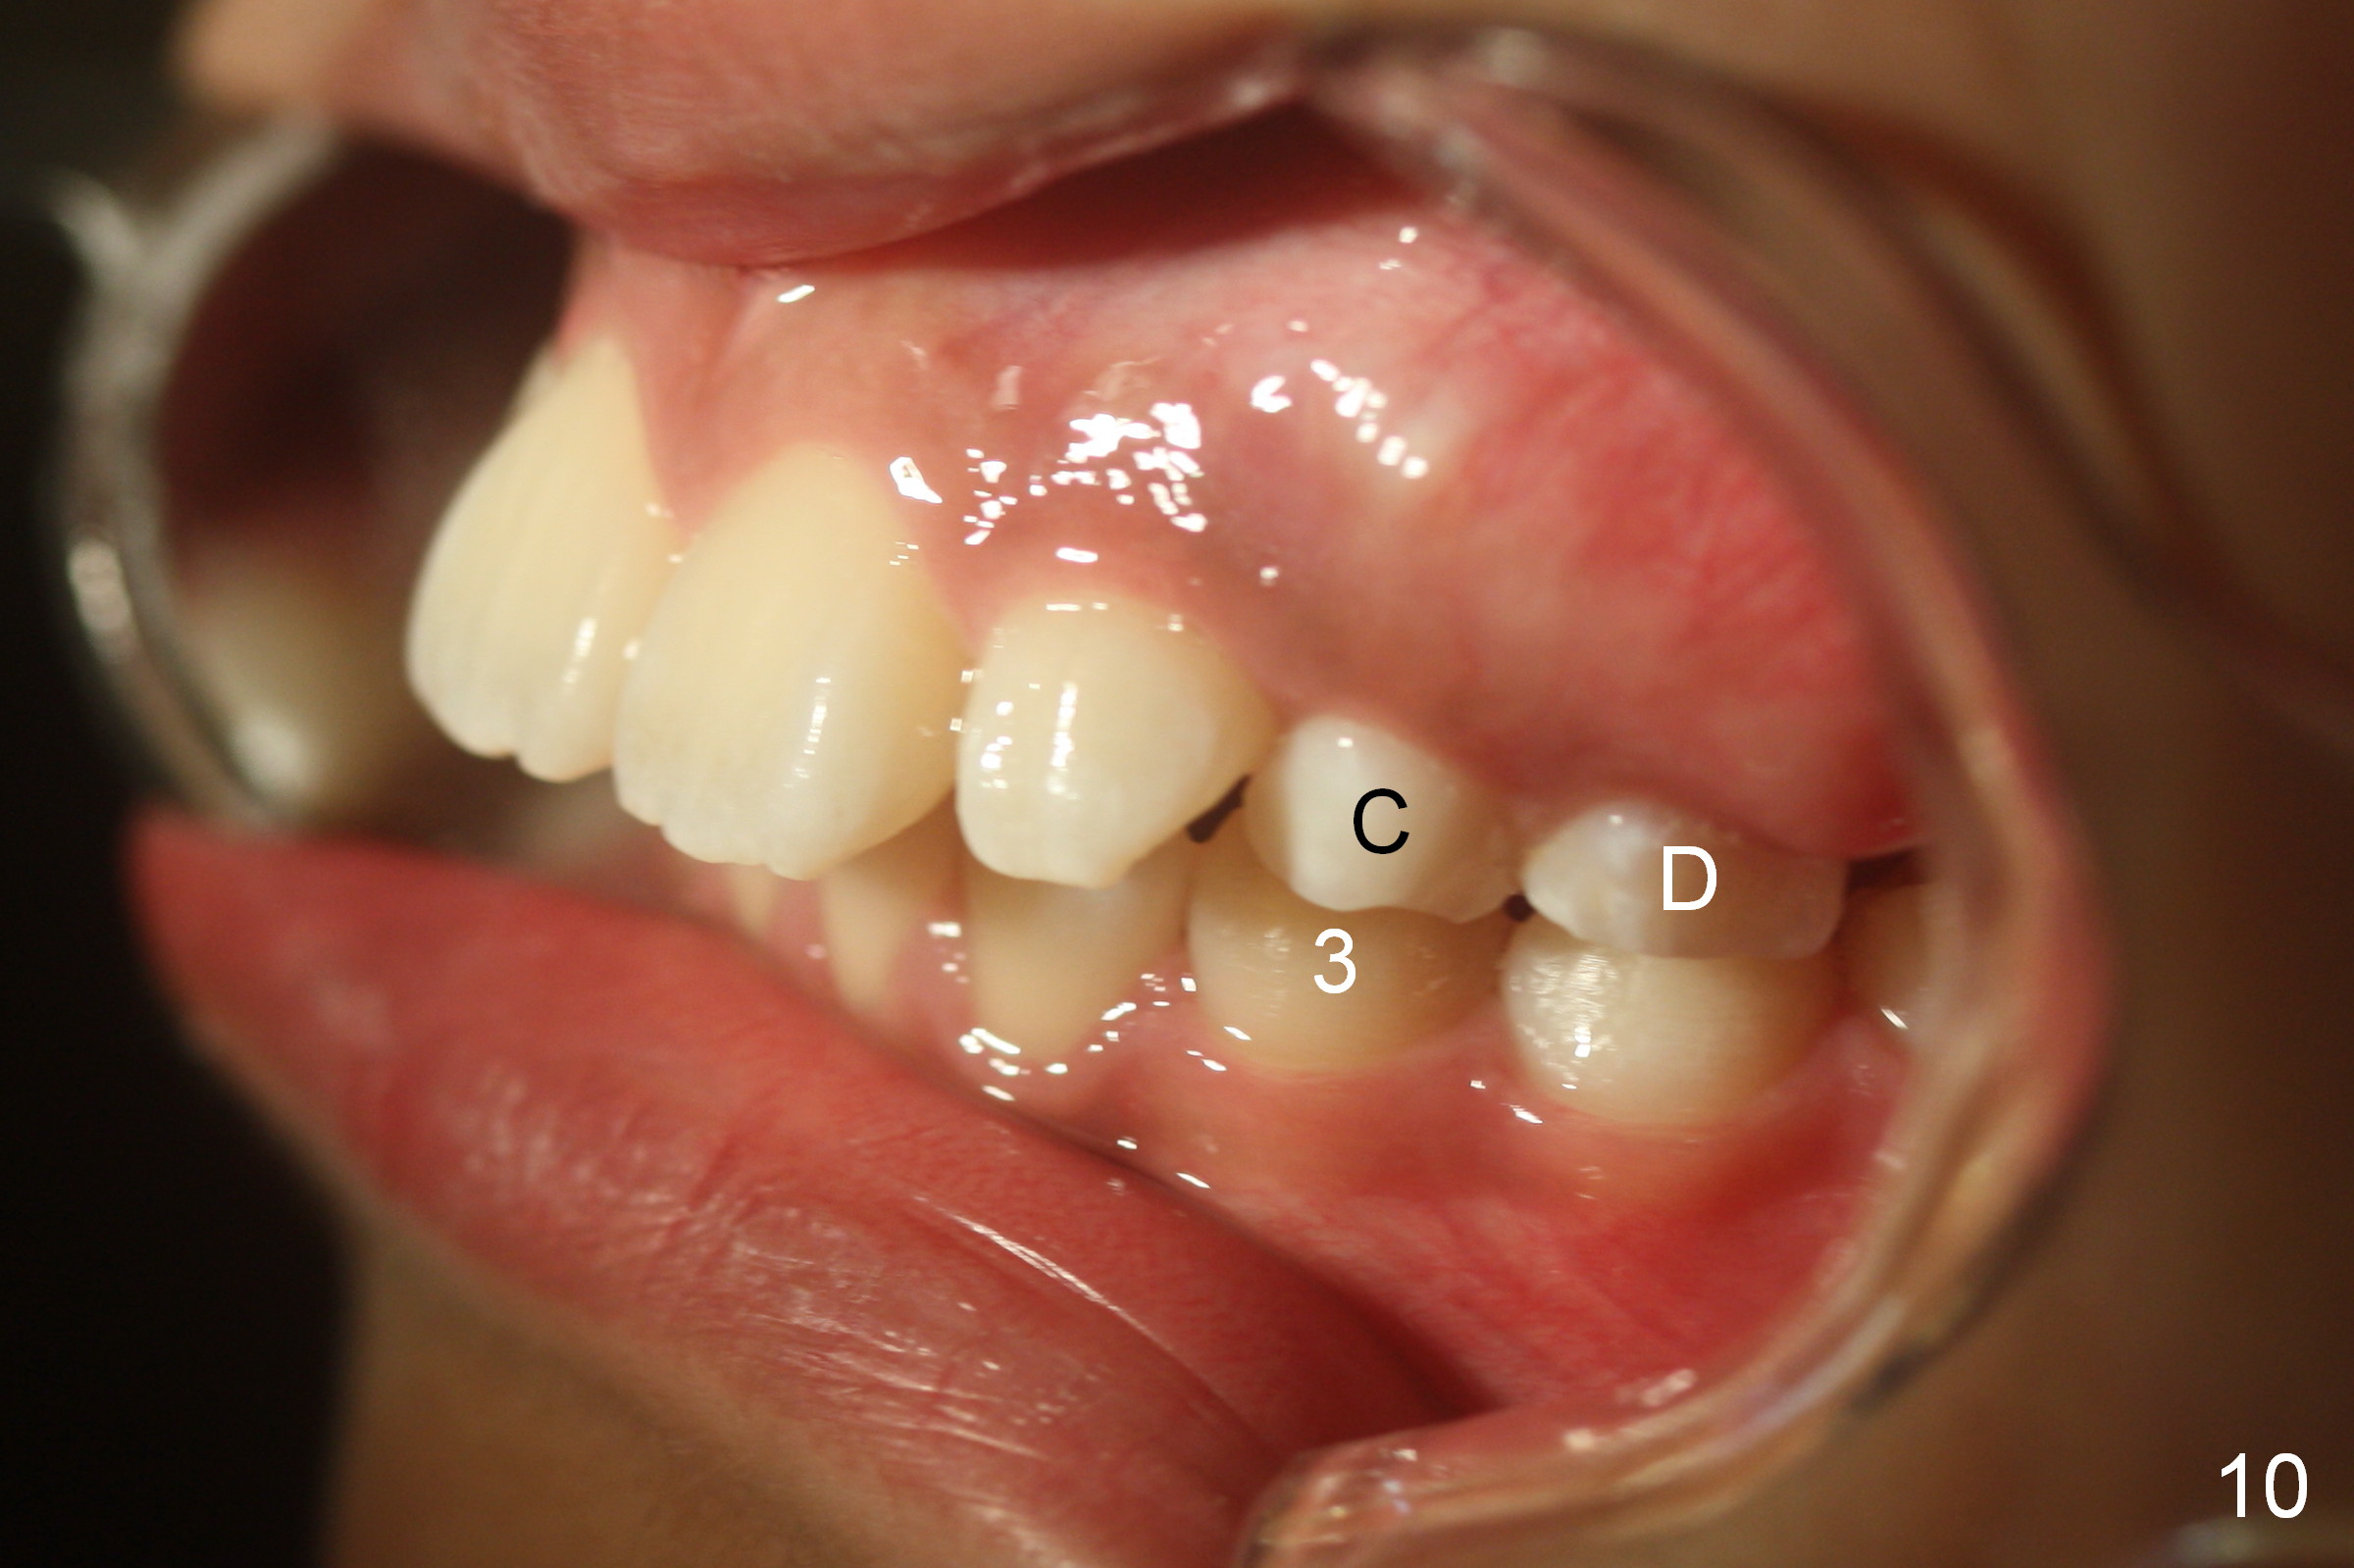

A 11-year-old boy has history of asthma. His father has sleep apnea with similar Class II malocclusion. Pan was taken for the boy 3 years ago (Fig.1). His mother wants to have orthodontic treatment as early as possible, because of protrusive upper anterior teeth. The dentition is permanent except the upper left canine and 1st molar (Fig.7,10,12,13 C, D). It appears that there is bilateral Class II occlusion at canine by half a tooth (Fig.9-12). The malocclusion and facial profile can be easily corrected with extraction of the upper 1st bicuspids.